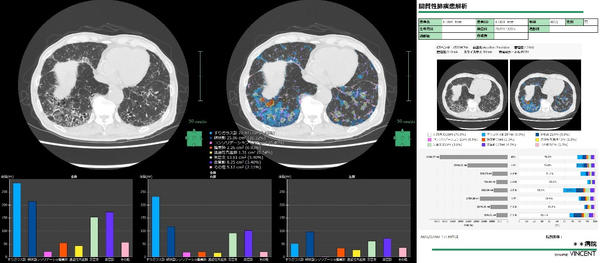

2025年にリリースした間質性肺疾患解析*6にも新たにレポート機能を搭載し,CT画像から定量評価した結果をレポートとしてアウトプットする一連のフローを「SYNAPSE VINCENT」で行うことができるようになる。

間質性肺疾患解析画面・レポート